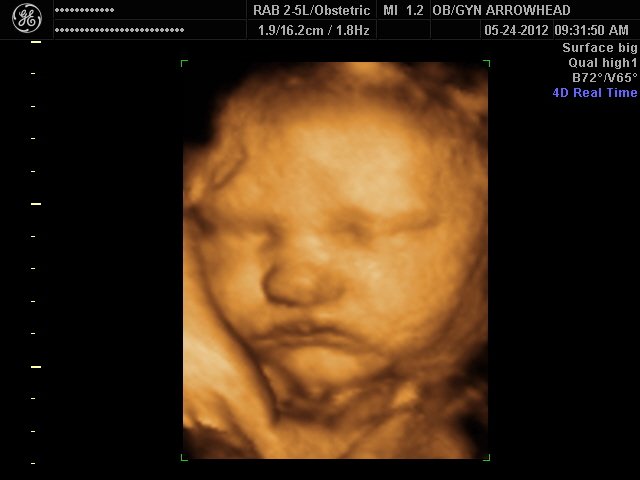

We offer complimentary 3D/4D Ultrasounds to all our OB patients around 30 weeks! The following photos are some examples of our work, shown with permission from our patients.